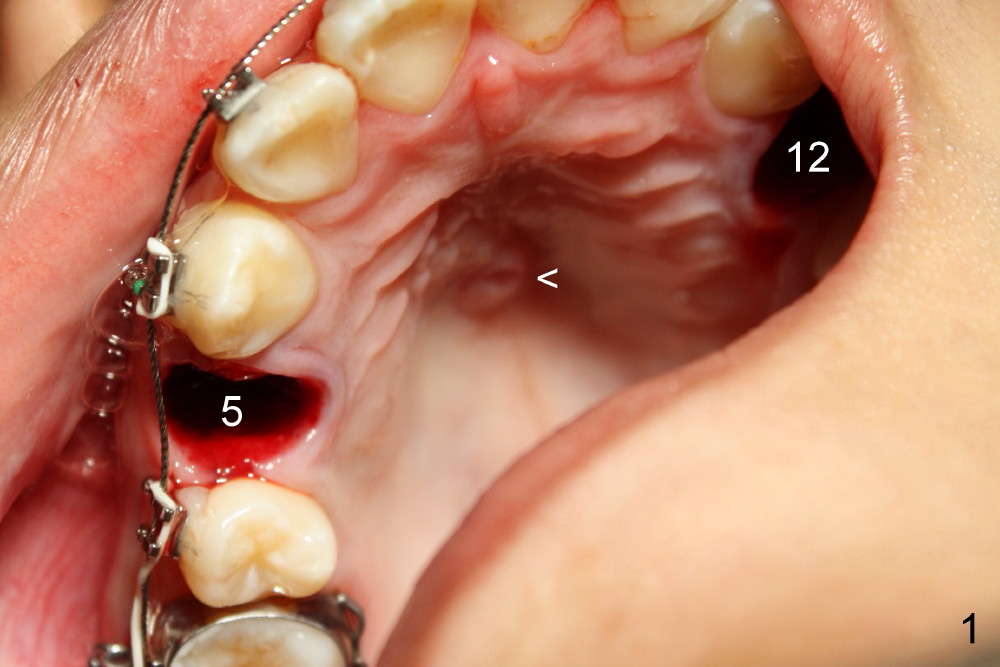

The mini-implant in the para-sagittal palate is loose, losing its anchorage. In fact the upper incisors are pushed forward using open coils springs. The T-wire and the mini-implant (Fig.1 <) are removed. A flexible wire is placed; two upper bicuspids are extracted (#5,12).